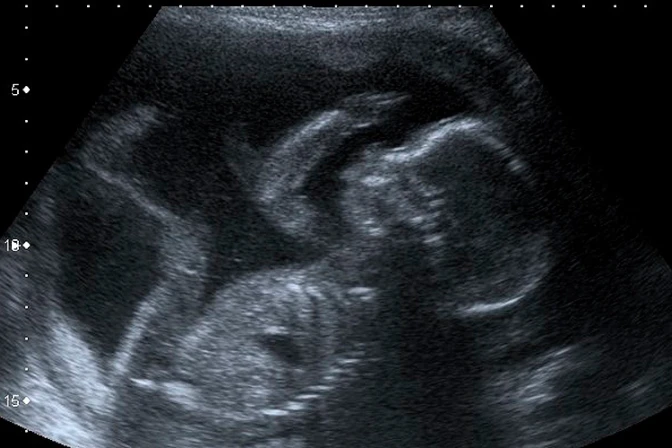

"Cuando se trata de este particular tipo de aborto, la gente necesitaba escuchar exactamente lo que se estaba haciendo: bebés en el segundo trimestre, estamos hablando de tres, cuatro, cinco meses de embarazo, estaban siendo desgarrados, miembro a miembro", señaló.